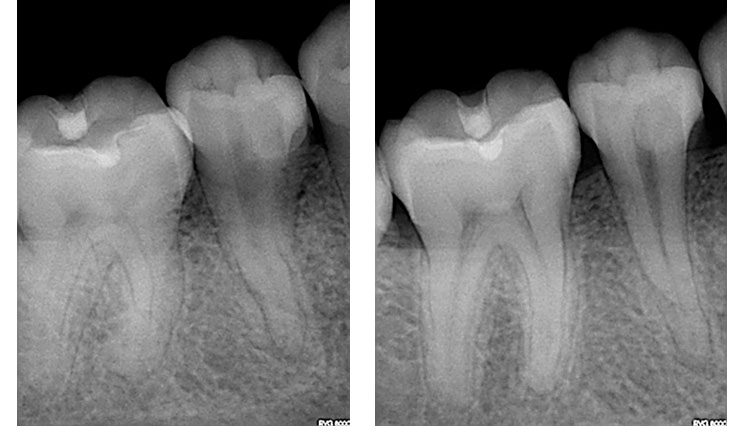

왼쪽 2개의 사진에서 치아가 2개 있는데요, 둘 중에 오른쪽 치아가 괴사된 치아입니다. 그리고 오른쪽 2개의 사진은 신경치료를 한 치아의 엑스레이 사진입니다.(출처: https://zarc4endo.com/)